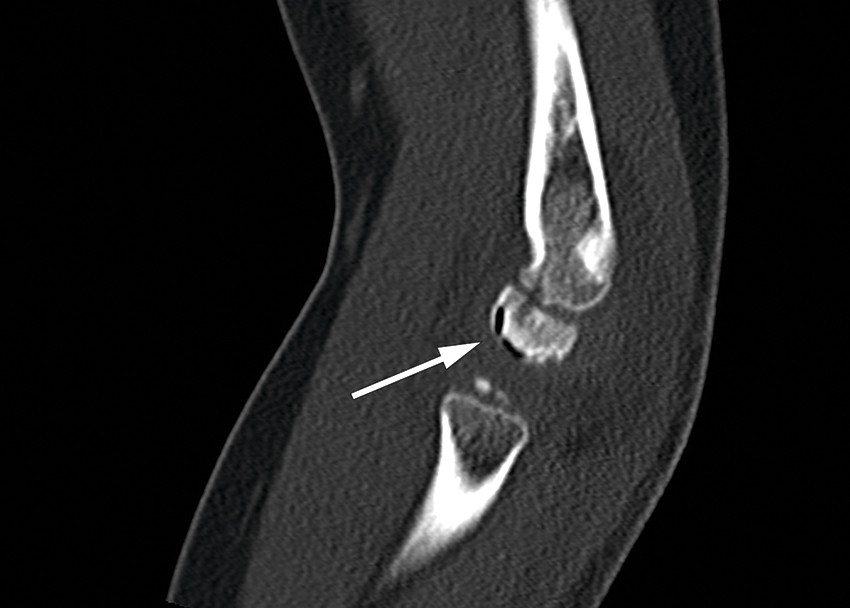

På røntgenbildet samsvarer oppklaringslinjen (markert med sort pil) med flere små gassbobler på samme sted på CT-bildet (hvit pil) - såkalt vakuumfenomen. Løftet fremre og bakre fettpute (markert med stjerner) er tegn på hydrops. Det er også litt ujevn benkontur ventralt i capitulum. Funn er typisk for Panners sykdom.

Røntgenbildet av venstre albue viser løftede fettputer som tegn på hydrops (markert med stjerner), men ingen synlig fraktur eller luksasjon. Det ses en tynn stripe med redusert bentetthet subkondralt i ventrale del av capitulum (sort pil), og på CT-bildet samsvarer linjen med flere små gassbobler på samme sted – såkalt vakuumfenomen. Det er også ujevn benkontur ventralt i capitulum. Funnene er typisk for Panners sykdom.

CT-bilde. Vakuumfenomen er markert med hvit pil.